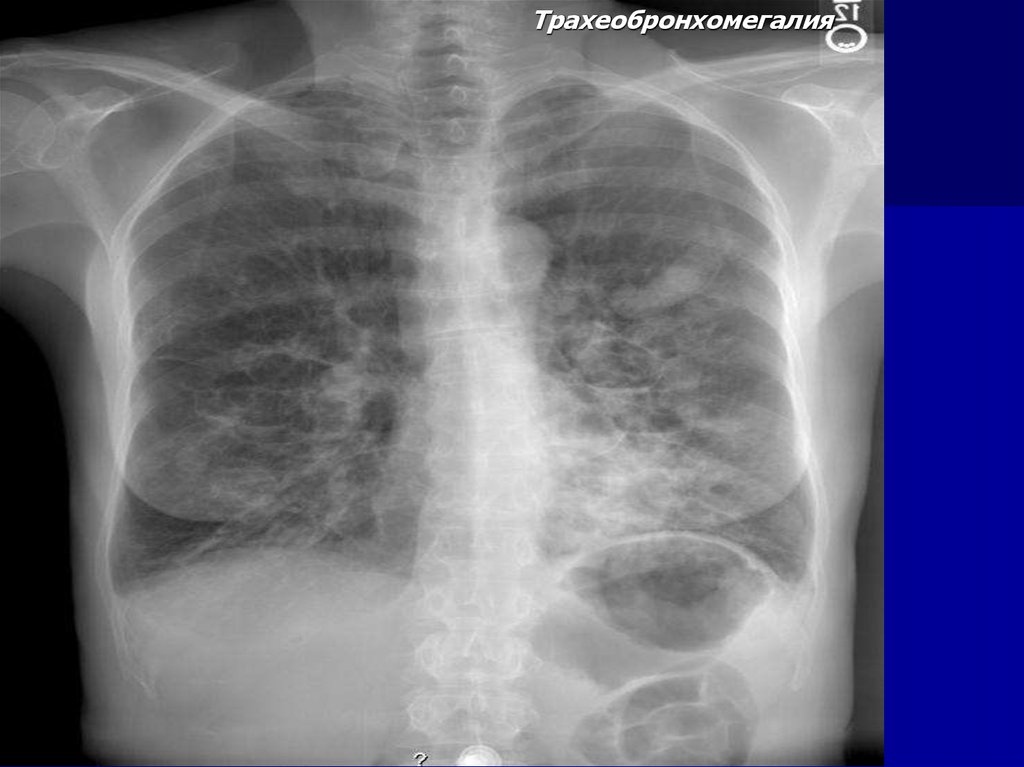

Трахеобронхомегалия